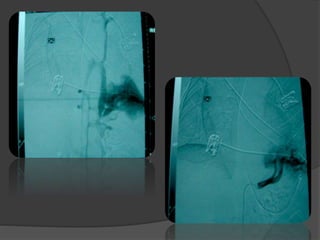

IMAGERIE

 IRM: l’artère systémique par l’angio-IRM

mais n’étudie pas le parenchyme.

 L’artériographie:1er temps d’un

traitement endo-vasculaire.